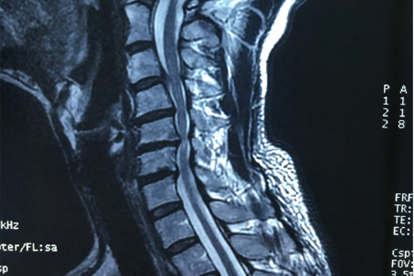

颈椎病多因长期不良姿势、劳损或退行性病变引起,表现为颈肩疼痛、头晕等症状,需及时就医避免病情加重。以下为成都地区治疗颈椎病较好的医院信息:

四川省人民医院骨科在颈椎病治疗方面具有特色优势,开展颈椎前路减压融合术、人工椎间盘置换术等技术。医院配备3.0T磁共振等高端设备,为诊断提供保障。